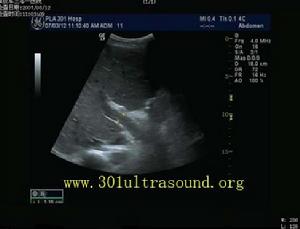

2、B超腹部B超可對多數病例做出初步正確診斷,其符合率可達95%以上。可在膈面頂部、第二肝門處探測肝靜脈及下腔靜脈阻塞的部位和長度以確定是否隔膜型。急性BuddChiari綜合徵時肝臟腫大和腹水多是突出的表現。都卜勒超聲對具有很高的診斷價值。因此,腹部超聲探查是BuddChiari綜合徵應首選的、有價值的、非創傷性檢查。

2檢查方法儀器:美國AIL公司生產的HDI-3000型彩色都卜勒超聲診斷儀,凸陣探頭,頻率2~4MHz。患者空腹8~12h,仰臥位、左側臥位、必要時坐位,常規檢查肝臟大小、形態、內部回聲;測量肝靜脈、下腔靜脈內徑;觀察肝靜脈、下腔靜脈是否通暢,有無狹窄,周圍有無腫塊擠壓,腔內有無異常回聲,有無波動。彩色都卜勒及脈衝都卜勒觀察肝靜脈下腔靜脈血流色彩、頻譜形態、血流速度。聲束與血流夾角60°,腹水多者如影響觀察要抽水後複查。

1、布-加氏綜合徵的超聲特點從本組資料觀察布-加氏綜合徵有以下特點:肝靜脈近段狹窄或閉塞,內有膜性或實質性阻塞物,狹窄處血流變細,閉塞時血流消失,遠段血流淤滯擴張,擴張的肝靜脈血流方向異常或速度減慢。肝靜脈間交通支形成、擴張,副肝靜脈開放擴張。都卜勒可見肝靜脈狹窄處呈花彩血流,流速增加,頻譜異常,三相波消失呈平直形。下腔靜脈近心段狹窄或閉塞。表現局部管腔變細、消失,管腔內有膜性、實質性梗阻物或腔外有腫瘤壓迫。下腔靜脈狹窄處近側呈花彩血流,速度增快,本組最高流速達260cm/s,或管腔內無血流信號。狹窄遠側管腔擴張,周圍側支循環豐富,血流方向異常流入側支。下腔靜脈波動消失,頻譜平直。

2、誤診分析本組超聲誤診2例。1例平臥位檢查下腔靜脈近段內徑0.4cm,流速增快250cm/s,坐位時內徑0.55cm,流速100cm/s,肝腫大,肝靜脈擴張,唆水。經保肝利尿治療後,肝臟縮小,腹水消失。複查下腔靜脈內徑0.9~1.0cm,流速100cm/s。最後診斷:酒精性肝硬化。另1例下腔靜脈近心段內徑1.0cm,臥位呈花彩血流,坐位呈單色血流,流速145cm/s,肝明顯腫大,肝靜脈擴張。經治療後肝縮小,腹水及下肢浮腫消失,最後診斷:腎病綜合徵。分析此2例是肝腫大重力後壓引起下腔靜脈狹窄。改變體位,減輕肝對下腔靜脈的壓迫,可使下腔靜脈增寬,流速降低。這種變化可以作為鑑別診斷要點。目前國內有採取俯臥位或近俯臥位經肋間觀察下腔靜脈,但患者往往難以接受。我們認為坐位是一種較好的鑑別診斷方法。另一方面,此2例僅有肝靜脈擴張,未見交通支和副肝靜脈擴張,說明肝靜脈通暢或間歇性通暢,李傑等曾報告布―加氏綜合徵中副肝靜脈的意義,從本組誤診情況來看,觀察肝靜脈交通支特別是副肝靜脈有無擴張對布-加氏綜合徵的鑑別診斷有重要價值.